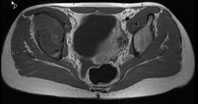

Die Röntgenuntersuchung von Becken/Hüfte zeigt eine septierte geographische Osteolyse in der Ala und im Korpus des Os Iliums rechts. Das Röntgenbild und die Aufnahmen der nachfolgenden MRI-Untersuchung sehen Sie hier: